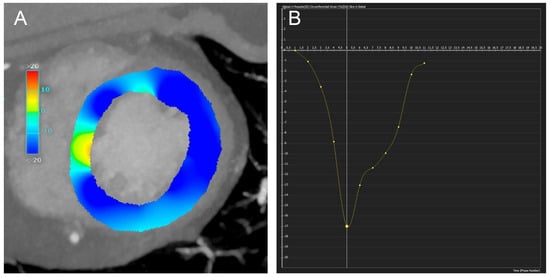

3.2.4. Strain Measurement

- Manohar, A.; Colvert, G.M.; Ortuño, J.E.; Chen, Z.; Yang, J.; Colvert, B.T.; Bandettini, W.P.; Chen, M.Y.; Ledesma-Carbayo, M.J.; McVeigh, E.R. Regional left ventricular endocardial strains estimated from low-dose 4DCT: Comparison with cardiac magnetic resonance feature tracking. Med. Phys. 2022, 49, 5841–5854. [Google Scholar] [CrossRef]

- Wang, R.; Fang, Z.; Wang, H.; Schoepf, U.J.; Emrich, T.; Giovagnoli, D.; Biles, E.; Zhou, Z.; Du, Z.; Liu, T.; et al. Quantitative analysis of three-dimensional left ventricular global strain using coronary computed tomography angiography in patients with heart failure: Comparison with 3T cardiac MR. Eur. J. Radiol. 2021, 135, 109485. [Google Scholar] [CrossRef] [PubMed]

- Tanabe, Y.; Kido, T.; Kurata, A.; Sawada, S.; Suekuni, H.; Kido, T.; Yokoi, T.; Uetani, T.; Inoue, K.; Miyagawa, M.; et al. Three-dimensional maximum principal strain using cardiac computed tomography for identification of myocardial infarction. Eur. Radiol. 2017, 27, 1667–1675. [Google Scholar] [CrossRef] [PubMed]

- Manohar, A.; Colvert, G.M.; Yang, J.; Chen, Z.; Ledesma-Carbayo, M.J.; Kronborg, M.B.; Sommer, A.; Nørgaard, B.L.; Nielsen, J.C.; McVeigh, E.R. Prediction of Cardiac Resynchronization Therapy Response Using a Lead Placement Score Derived from 4-Dimensional Computed Tomography. Circ. Cardiovasc. Imaging 2022, 15, E014165. [Google Scholar] [CrossRef]